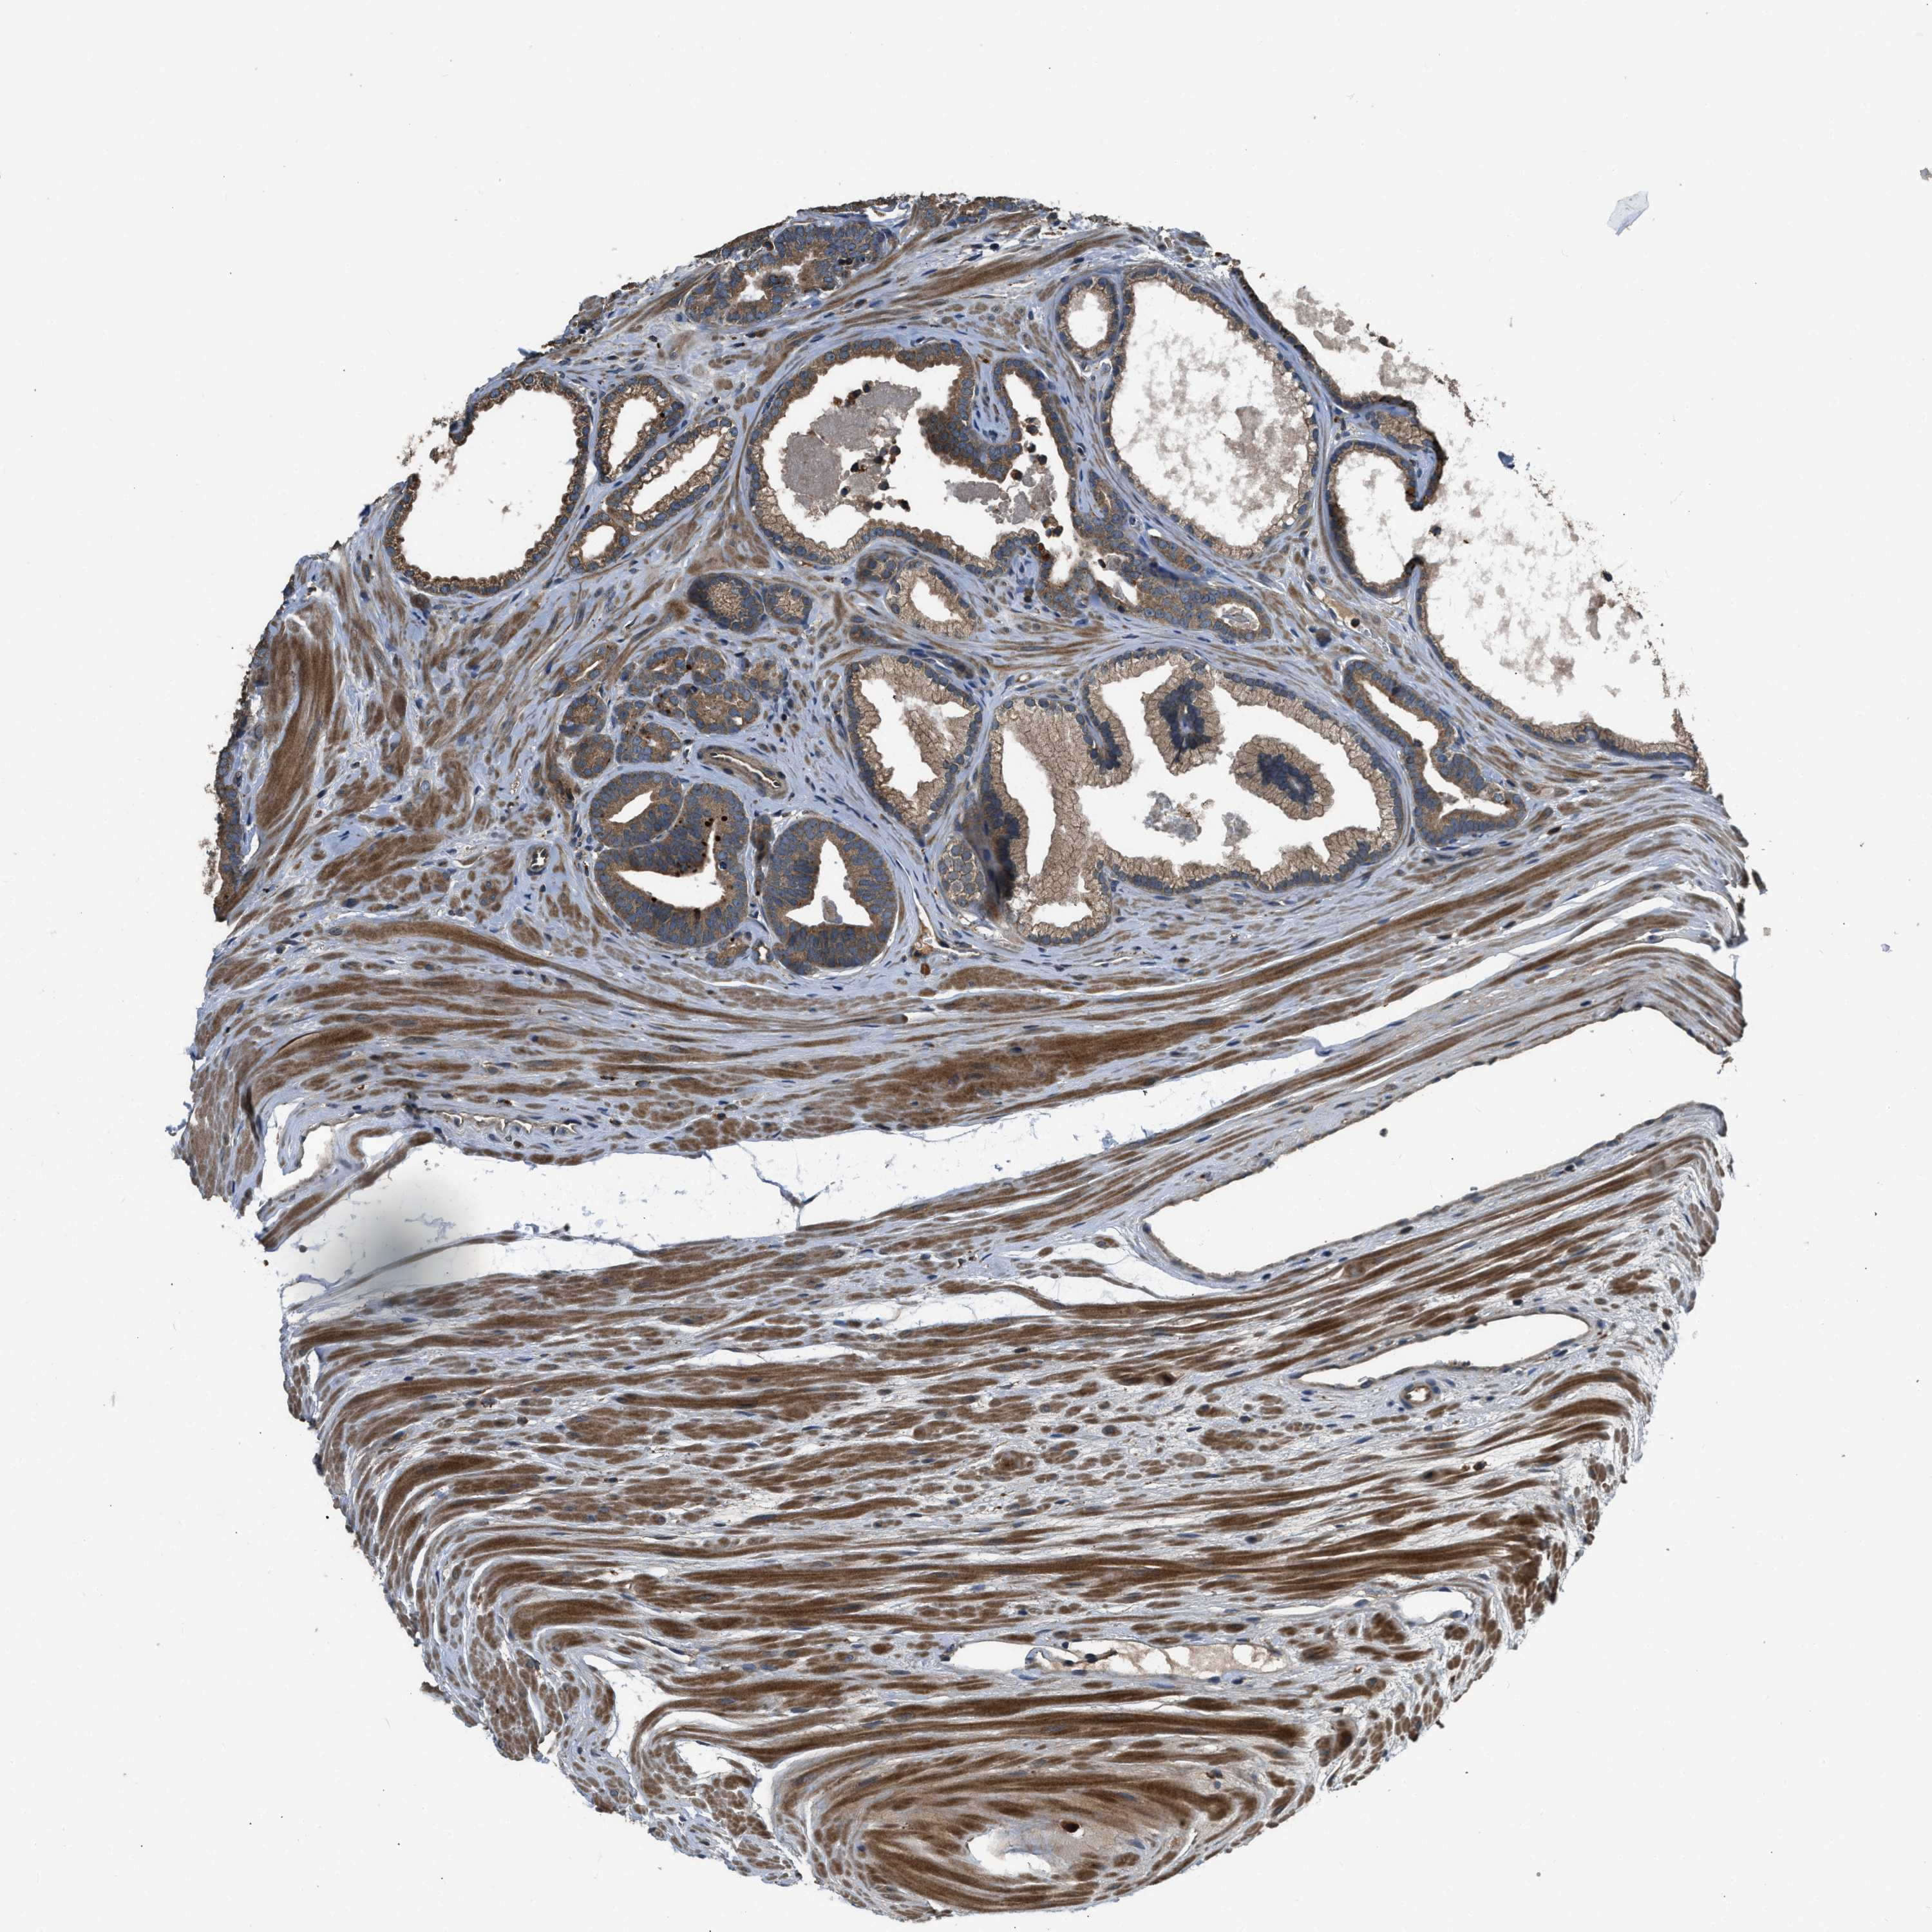

PROSTATE CANCER - Protein expressioni

A mouse-over function shows sample information and annotation data. Click on an image to view it in a full screen mode. Samples can be filtered based on level of antibody staining by selecting one or several of the following categories: high, medium, low and not detected. The assay and annotation is described here.

Note that samples used for immunohistochemistry by the Human Protein Atlas do not correspond to samples in the TCGA dataset.

Antibody stainingi

Antibody staining in the annotated cell types in the current human tissue is reported as not detected, low, medium, or high, based on conventional immunohistochemistry profiling in selected tissues. This score is based on the combination of the staining intensity and fraction of stained cells.

Each image is clickable and will lead to virtual microscopy that enables deeper exploration of all samples and also displays staining intensity scores, fraction scores and subcellular localization as well as patient and tissue information for each sample.

Antibody HPA025226

Antibody CAB019296

Staining

High

Medium

Low

Not detected

Intensity

Strong

Moderate

Weak

Negative

Quantity

>75%

75%-25%

<25%

None

Location

Nuclear

Cytoplasmic/membranous

Cytoplasmic/membranous,nuclear

Adenocarcinoma, High grade

Adenocarcinoma, Low grade